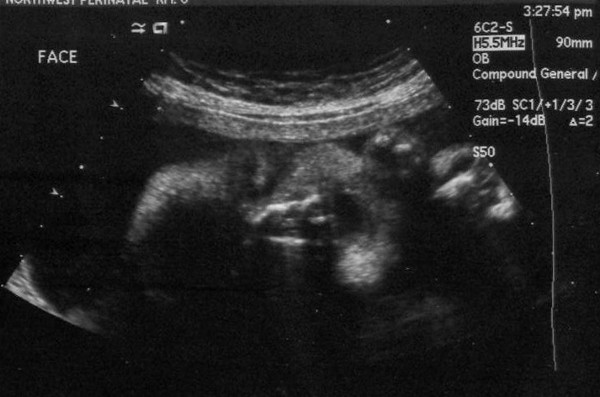

We had yet another ultrasound today. The baby's weight is estimated at 2 pounds 3 ounces which puts him in the 50th percentile for his gestational age -- right at average in other words. The sonographer made a comment about how she had to chase the baby around to get the measurements she wanted. It made me think... if she has to chase him around now, when he's in a very enclosed space, what does that imply about how much we'll have to chase him when he learns to crawl and walk?

Here is the picture of his face that we got today. Not quite as clear as the one two weeks ago but still very recognizable. It looks like he's laughing to me with the way he has his mouth open.